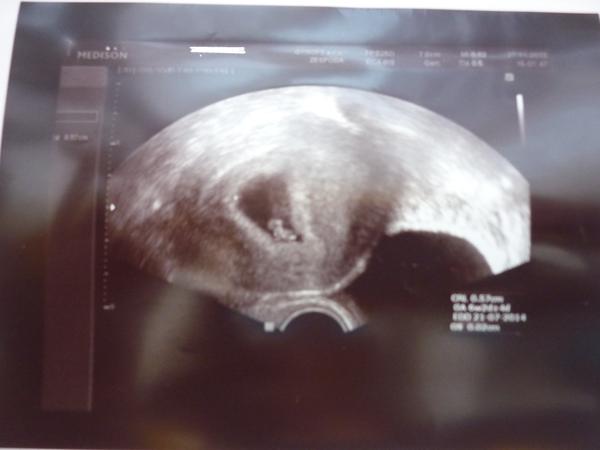

@ofina1 vše v pořádku,odpovídáme 6+2,srdíčko buší🙂víc jsem si ani nemohla přát...

@petulaho jupííííí tak to je nádherná zpráva strašně moc ti to přeju 🙂 🙂 krásná fotečka !!!!

@petulaho juuuu.... Moc, moc gratuluji, krásná fotečka z ultrazvuku, jen tak dále čím víc takových zpráv, tím líp 🙂

@petulaho Mám velikou radost 🙂 ,máš krásnou fotku

@petulaho Peti, moc a moc gratuluju, krasna zprava a jeste krasnejsi fotecka. 🙂

@petulaho Nádhera a už i srdíčko na začátku sedmého týdne, to je parádička. Bude to silný a zdravý prcek🙂 Peťulko, tak letos budou krasné Vánoce vid? Tak se moc opatruj a zadne bacily na sebe nepusť. A v lete uz se tesim az toho prcka uvidim🙂